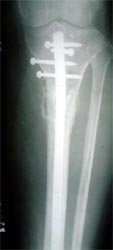

病例三、患者男性,25岁,胫骨下段骨不连3年

图3 病例三、患者男性,25岁,胫骨下段骨不连3年。我们用异体骨板提供支撑力,植如患者自体骨髓细胞经与松质骨和骨生长因子复合物,骨折在9个月后愈合。